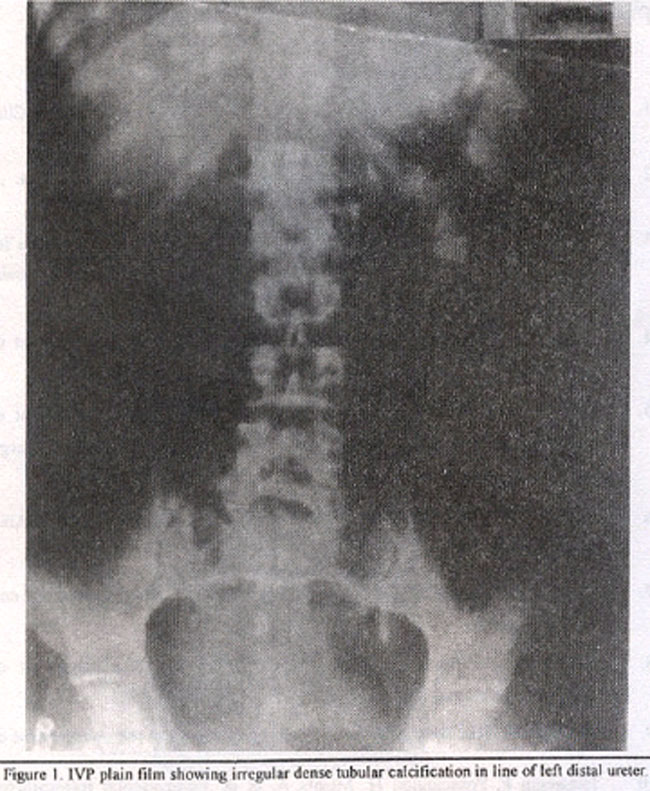

A 55 years old male, known case of genitourinary tuberculosis, presented with fever, abdominal pain and pyuria. On examination he was tender in left lumbar area. Laboratory findings showed increased white cell count of 15,000and increased ESR. Urine analysis revealed frank pus with few red blood cells. Plain film of the abdomen showed irregular dense calcification in the left renal area opposite the transverse processes of L1-L3 vertebral bodies. There was also dense tubular calcification in line of left distal ureter (Figure 1).